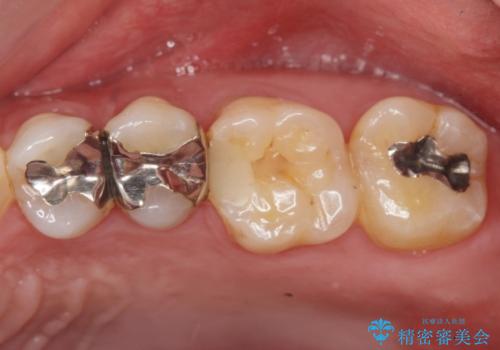

ジルコニアクラウン(被せもの)で治療を行いました。

- 仮歯・ジルコニアクラウン 12.1万円費用は治療当時の料金となります

銀の詰め物はかなり昔に治療されたそうです。

銀の詰め物は虫歯の再発リスクが高く、歯に痛みが出てしまうと歯の神経の治療もしないとならなくなってしまいます。

定期的なメンテナンスを行うことが大切です。